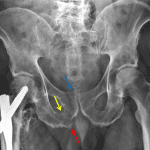

- Acute nondisplaced fractures of the right superior and inferior pubic rami

- Acute nondisplaced fracture of the right pubic body with extension into the pubic symphysis

- Inferiorly distracted avulsion fracture from the medial aspect of the right ischial tuberosity

- Partially imaged cephalomedullary nail fixation of a remote right intertrochanteric femoral fracture with a superioly displaced lesser trochanteric fragment and surrounding heterotopic ossification

Acute nondisplaced fractures of the right superior and inferior pubic rami.

Acute nondisplaced fracture of the right pubic body with extension into the pubic symphysis. No joint malalignment or diastasis.

Inferiorly distracted avulsion fracture from the medial aspect of the right ischial tuberosity.

Partially imaged cephalomedullary nail fixation of a remote right intertrochanteric femoral fracture with a superiorly displaced lesser trochanteric fragment and surrounding heterotopic ossification.